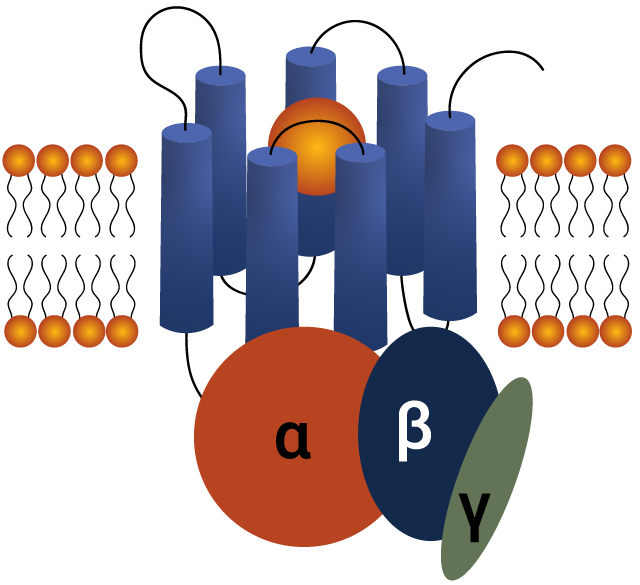

GPCRs: Key Drivers in Drug Discovery

G-protein-coupled receptors (GPCRs) are a diverse family of cell surface proteins critical for cellular communication. They regulate vital physiological processes and are the target of nearly 35% of all approved drugs. Their central role in disease pathways makes GPCRs essential for drug discovery, offering opportunities to develop treatments for cancer, cardiovascular and neurological disorders.